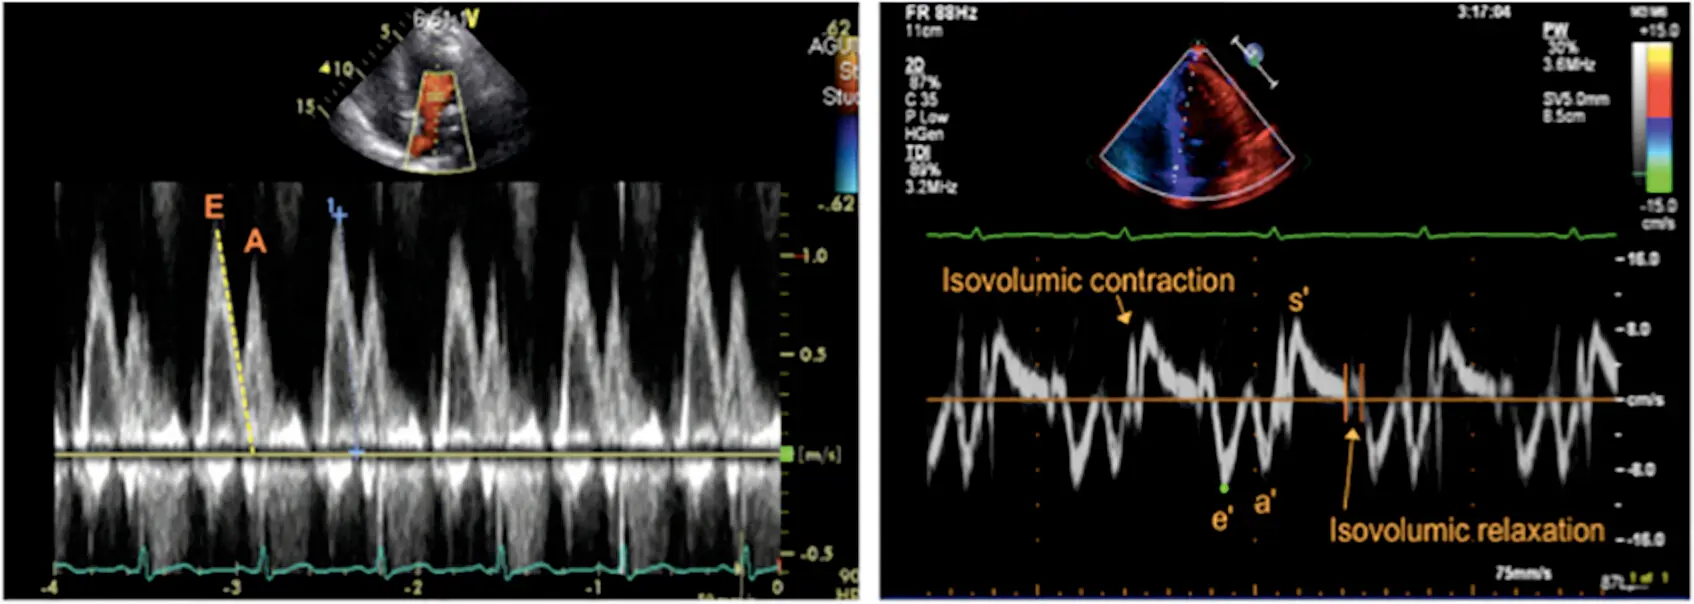

Mitral inflow velocity: Peak E-wave velocity (cm/s) is the peak early diastolic modal velocity after ECG T wave

Mitral inflow velocity: Peak A-wave velocity (cm/s): peak late diastolic modal velocity after ECG P wave

Mitral annular velocity: e’ velocity (cm/s): peak early diastolic modal velocity after ECG T-wave

Mitral annular velocity: a’ velocity (cm/s): peak late diastolic modal velocity after ECG P-wave

E velocity on mitral inflow is preload-dependent, whereas the mitral annulus e’ velocity as a marker for LV relaxation is preload-independent.

- ==E mitral inflow velocity increases with severity of diastolic dysfunction==

- This characteristics also allows you to distinguish “pseudonormal” vs normal.

Isovolumic Relaxation Time (IVRT)

- IVRT is a good screening parameter for LA pressure, regardless of underlying LV ejection fraction.3

- IVRT is shortened when LA pressure increases.

- IVRT measures the time between aortic valve closure until mitral valve opening/inflow.

- If IVRT is prolonged (>100 ms), LA pressure is not elevated because the delay in mitral valve opening is related to lower pressure crossover between LV and LA in the setting of delayed relaxation.3

- In other words, a longer duration of IVRT (closure of AV to mitral inflow) on mitral inflow suggests normal filling pressures

- If LA pressure is elevated even with abnormal myocardial relaxation, the mitral valve opens at a high pressure, and IVRT gets shortened. ∴, it is safe to conclude that LA pressure is elevated if the IVRT is short (<60 ms) in the presence of cardiac disease. However, it is difficult to estimate LA pressure when IVRT is relatively normal.3

- In patients with impaired LV relaxation, IVRT <70 ms is usually associated with increased LA pressure.2